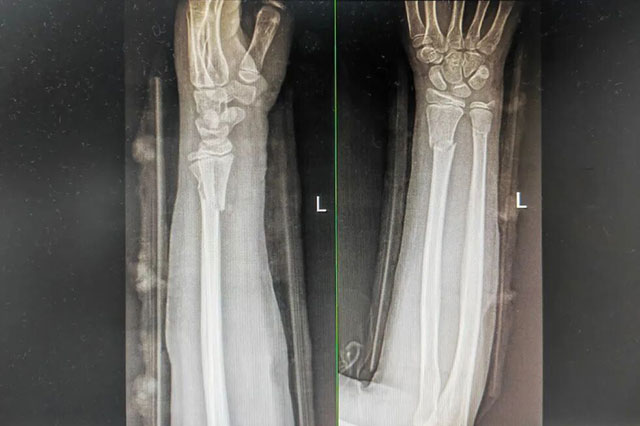

9岁的西安女孩小晗玩耍时意外摔倒,左手前臂以不自然角度扭曲。紧急送医后,X光片显示其尺桡骨双骨折,断端已移位。父母带她辗转当地多家医院,均建议手术复位。

次日,一家人跨越千里赶到正骨病房。此时付至江主治中医师刚结束治疗,便立刻接过病历和片子。他细细比对后,轻触小晗前臂检查,动作轻柔:“孩子骨骼柔韧,尺桡骨双骨折,首选中医正骨保守治疗……”

复查X光片显示,骨折断端复位良好。夕阳洒进病房,落在小晗的夹板上,也照亮一家人的笑脸。妈妈轻抚女儿的头:“这趟没白来,中医正骨太神奇了。”